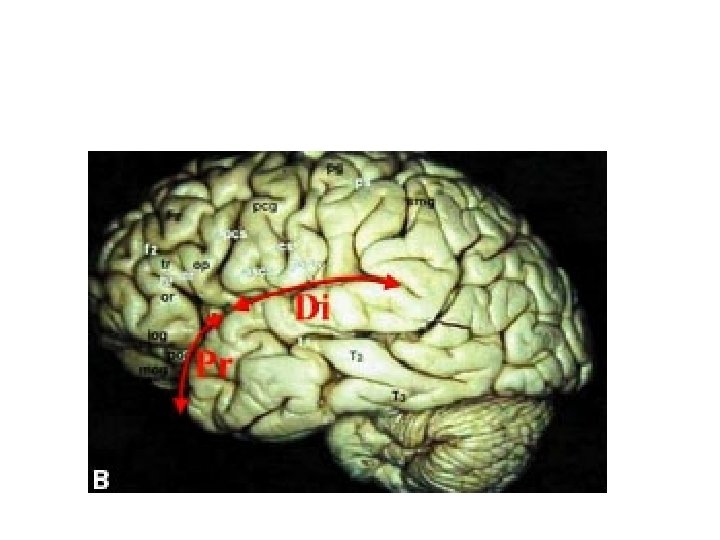

Sylvian fessure distal and prossimal division